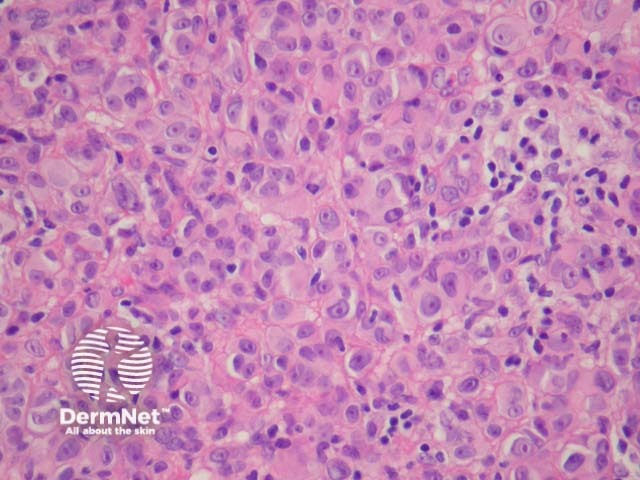

Figure 4